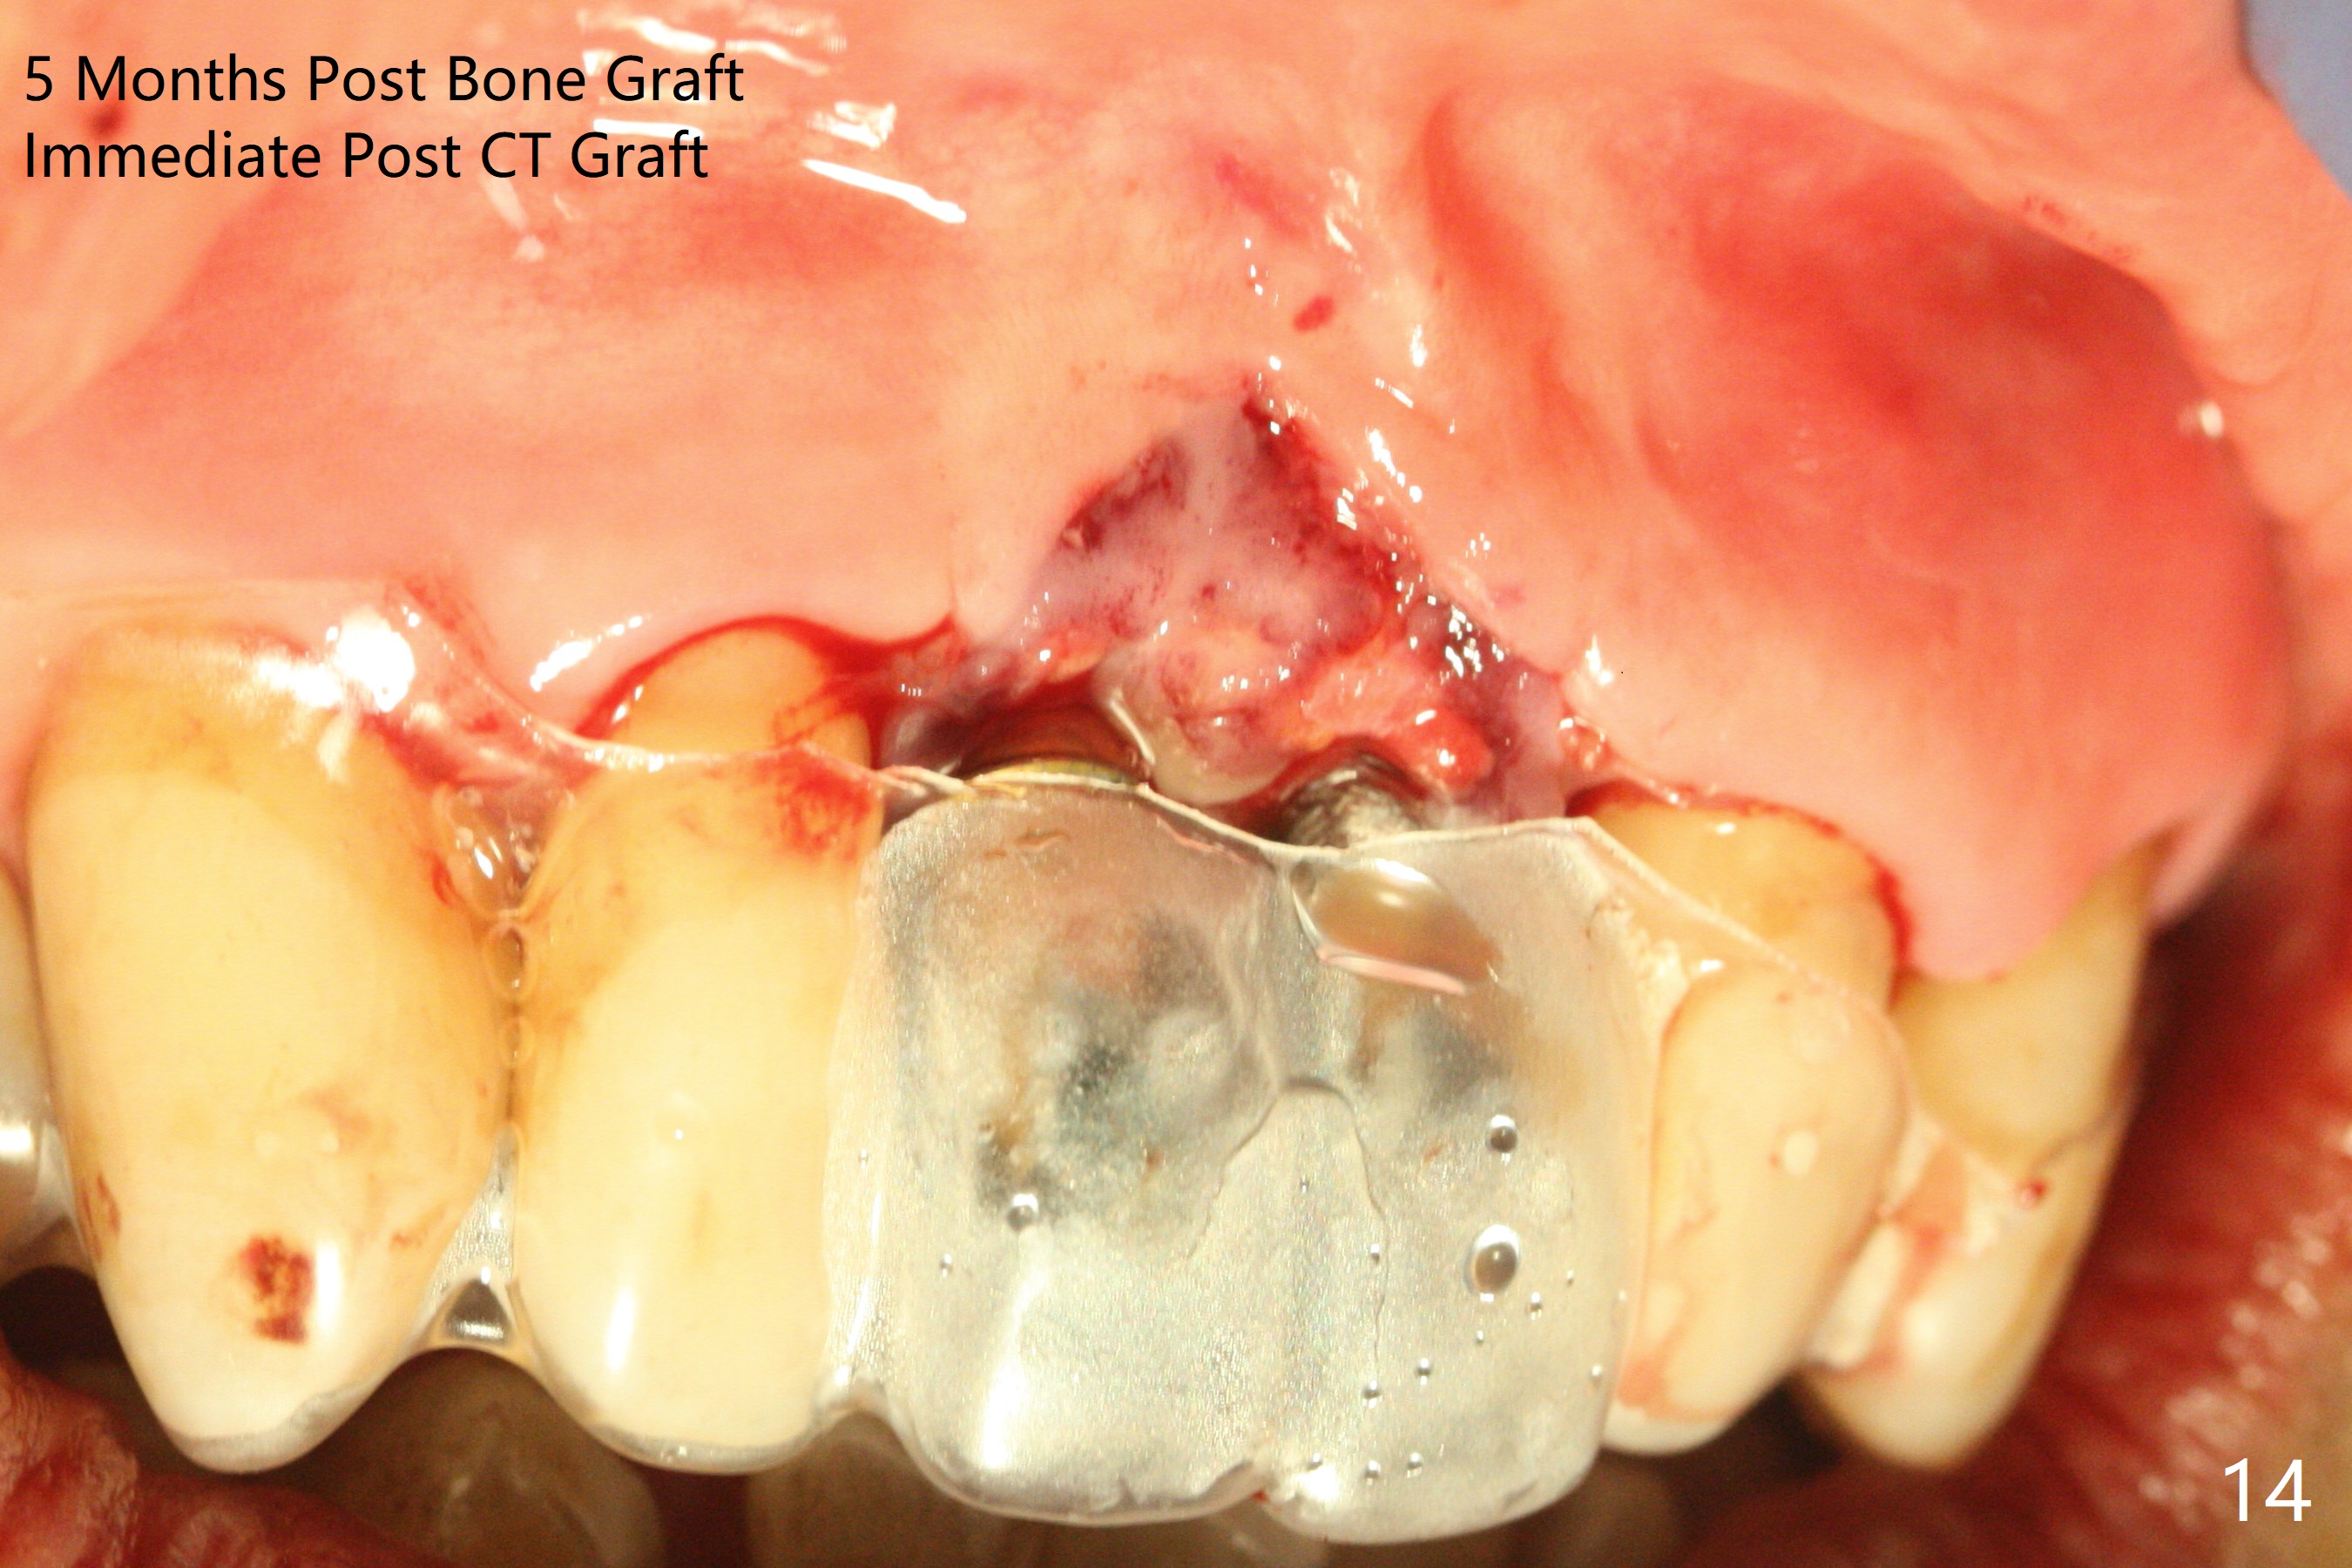

The gingiva remains recessive at #8 and 9 six months post immediate implant placement with bone graft (Fig.1). The buccal plate at #8 is particularly concave before (Fig.2 *) and after (Fig.3) abutment removal. The bony defect repair is assisted by placing a 4 mm tenting screw between the 2 implants (Fig.4) and placing allograft mixed with PRF (as putty) around the screw (Fig.5 (after replacement of the abutments)). The buccal contour improves because of the tenting screw and the bone graft placement (Fig.6 (as well as PRF and 6-month membranes)). The wound dehisces 12 days postop and immediately before leaving country for months (Fig.7). The sutures are removed, Osteogen plug is inserted (Fig.8) and periodontal dressing is applied (Fig.9). PA is taken to show the tenting screw (Fig.10 T). The latter is exposed 3 months postop (Fig.11,12). It appears that gingival graft is a must (Fig.13). Make a palatal stent, remove the temp with abutments and create a bleeding surface before harvesting a large piece of tissue. Connective tissue graft is done 5 months post bone graft (Fig.14). In fact there is no implant thread exposure. In fact the connective tissue graft does not survive. The abutments are re-prepared for pink porcelain (Fig.15). The bone loss is stable 1 year post cementation in spite of incomplete abutment seating (Fig.16). The soft tissue is nearly normal (Fig.17).